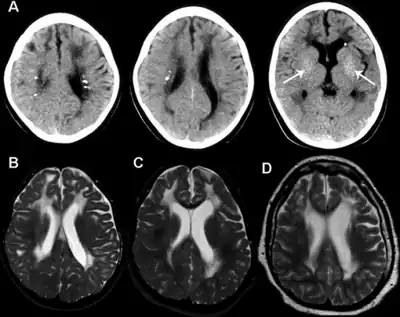

Neuroradiology: The spectrum of neuroradiological features associated with AGS is broad,[35][36] but is most typically characterised by the following:

- Cerebral calcifications: Calcifications on CT (computed tomography) are seen as areas of abnormal signal, typically bilateral and located in the basal ganglia, but sometimes also extending into the white matter. Calcifications are usually better detected using CT scans (and can be missed completely on MRI without gradient echo sequences (magnetic resonance imaging)).

- White matter abnormalities: These are found in 75-100% of cases, and are best visualised on MRI. Signal changes can be particularly prominent in frontal and temporal regions. White matter abnormalities sometimes include cystic degeneration.

- Cerebral atrophy: is seen frequently.

In 1984, Jean Aicardi and Francoise Goutières described eight children from five families presenting with a severe early onset encephalopathy, which was characterized by calcification of the basal ganglia, abnormalities of the cerebral white matter and diffuse brain atrophy.[1] An excess of white cells, chiefly lymphocytes, was found in the cerebrospinal fluid (CSF), thus indicating an inflammatory condition. During the first year of life, these children developed microcephaly, spasticity and dystonia. Some of the parents of the children were genetically related to each other, and the children were both male and female, which suggested that the disease was inherited as an autosomal recessive genetic trait.